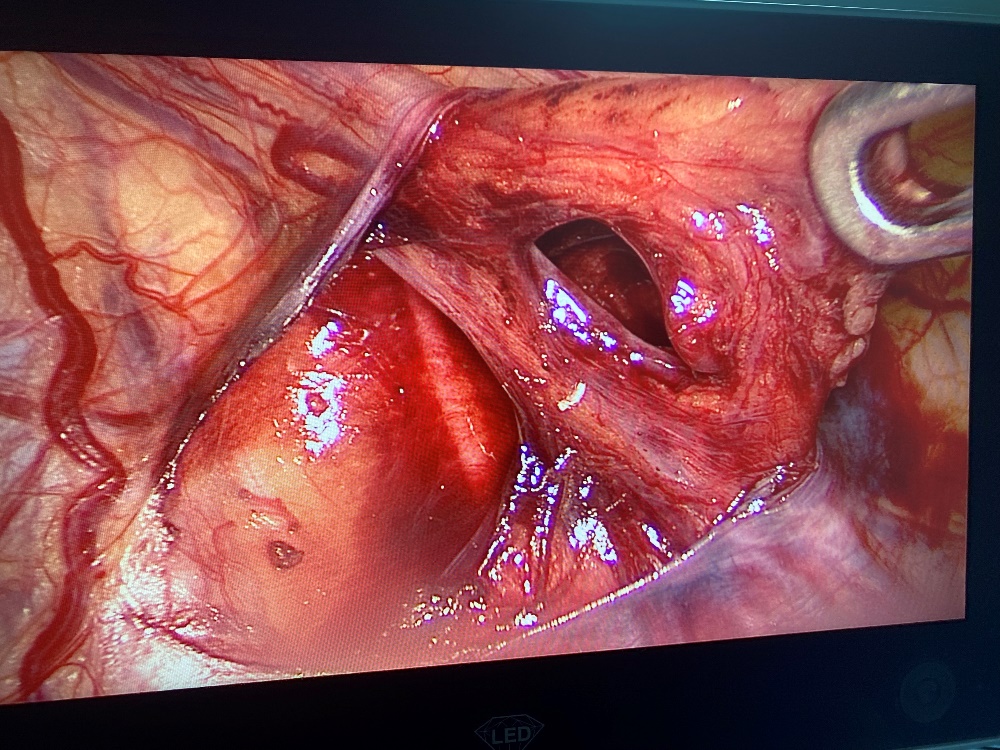

• Xác định tĩnh mạch tinh.

• Phẫu tích phúc mạc, bộc lộ động mạch, tĩnh mạch tinh kèm ống dẫn tinh.

• Tách chọn lọc tĩnh mạch tinh, thắt tĩnh mạch, bảo tồn động mạch, ống dẫn tinh.